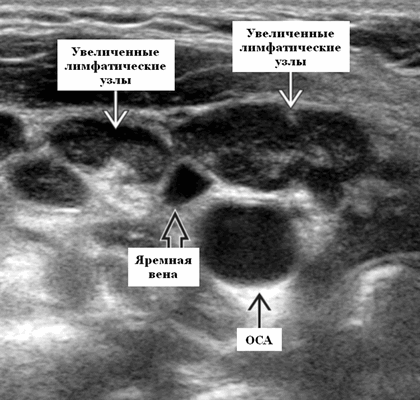

- Лучший диагностический ключ. Нормальный или слегка увеличенный лимфоузел в известном анатомическом положении. Другие реактивные узлы на шее, односторонние или двусторонние. Несколько хорошо очерченных, овальных узлов

- Расположение. Известно анатомическое расположение узлов в области шеи. Субментальные узлы, подчелюстные узлы, внутренние яремные узлы (от основания черепа до ключицы). Ретрофарингеальные узлы, дополнительные спинномозговые узлы (над ключицей, сзади от грудино-ключично-сосцевидной мышцы и впереди к трапециевидной мышце). Узлы переднего отдела шеи (между подъязычной и грудинной вырезкой и между сонной оболочкой), верхние средостенные узлы (под вырезкой грудины). Вовлекаются любые группы лимфоузлов головы и шеи в зависимости от места стимуляции антигена

- Размер. Широкий диапазон. Взрослый: часто ≤ 1,5 см. Ребенок: Реактивный узел может быть ≥ 2 см

- Морфология. Узел обычно овальный, а не круглый